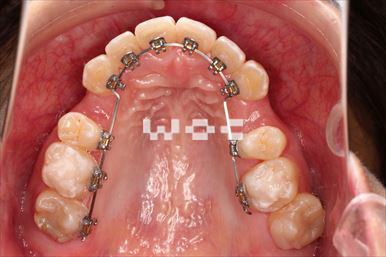

治療中3

出っ歯舌側矯正

上下舌側矯正を希望。

通院状況や歯みがきの協力が良かったため、1年7ヶ月で治療を終えることができました。※装置と注意事項に関しては、大人の矯正装置一覧へ。

- 年齢:20歳女性

- 主訴:出っ歯が気になる

- 基本矯正料金:120万円

- 治療期間:1年7ヶ月

- 抜歯部位:上顎両側第一小臼歯